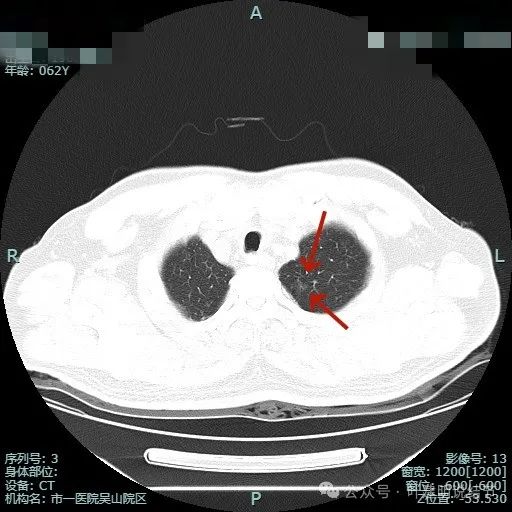

先看非薄层影像:

左上病灶出现,密度较淡,但轮廓较清。

密度不纯,有明显分叶。

有血管异常增粗与进入,边缘有细毛刺征。

血管穿行与表面浅分叶。